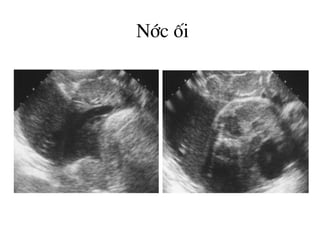

H×nh ¶nh cña níc èi

Níc èi